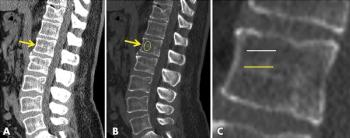

Radiologists should use this simple measure to detect osteoporosis when reading chest or abdominal CT scans and refer to orthopedic specialists for follow-up with positive findings.

Training sets from different vendors may be required to ensure scanner-specific sensitivity.